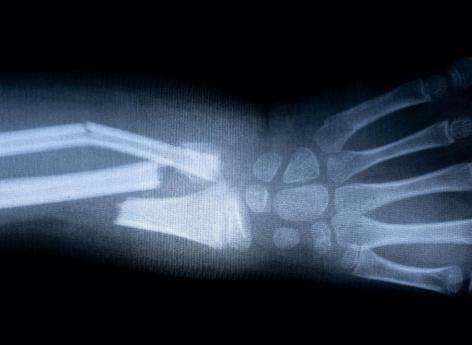

Pour les personnes ayant souffert de fractures, le processus de guérison prend généralement de 20 à 30 jours. Cette période pourrait bientôt être raccourcie grâce aux chercheurs de l'université de Purdue (Etats-Unis). Ils ont découvert un nouveau médicament injectable, dont les essais cliniques devraient débuter bientôt, qui vise à guérir pus rapidement les os fracturés et renforcer ceux qui sont faibles.

Ce nouveau médicament injectable sera utilisé pour traiter les fractures osseuses chez les adultes de plus de 60 ans lorsque le processus de guérison ralentit en raison du vieillissement. Les adultes âgés ayant subi une fracture de la hanche meurent généralement dans l'année qui suit. Avec ce nouveau médicament injectable, le retard de guérison pourrait devenir de l’histoire ancienne.